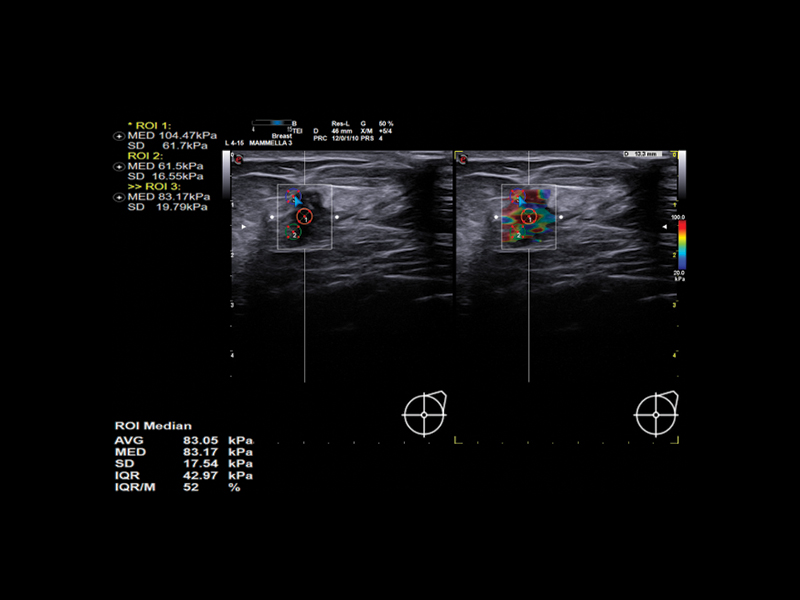

microV is Esaote’s new Doppler technology with an astonishing degree of sensitivity, even in very small vessels and slow flow detection; ElaXto, strain elastography, for real-time assessment of the relative stiffness of breast tissues; QElaXto 2D, 2D shearwave elastography, for mapping and quantification of tissue stiffness; and microE an algorithm for the enhancement of hyperechoic structures.

Clinical Images

Breast clinical image